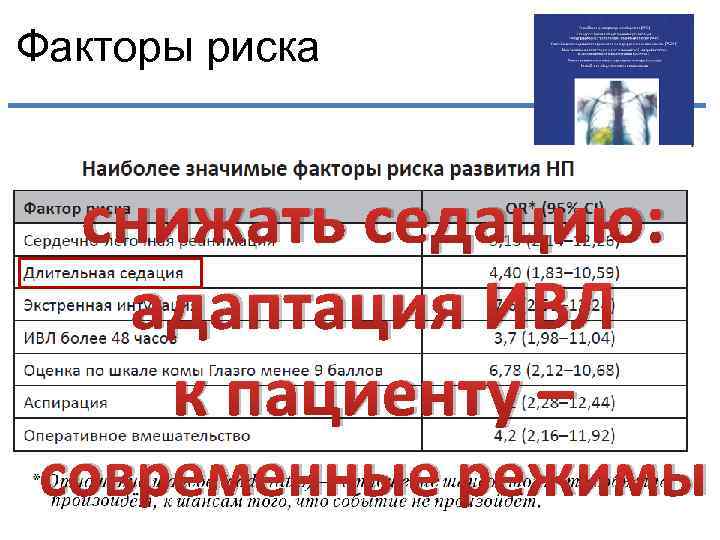

Факторы риска снижать седацию: адаптация ИВЛ к пациенту – современные режимы

Факторы риска снижать седацию: адаптация ИВЛ к пациенту – современные режимы